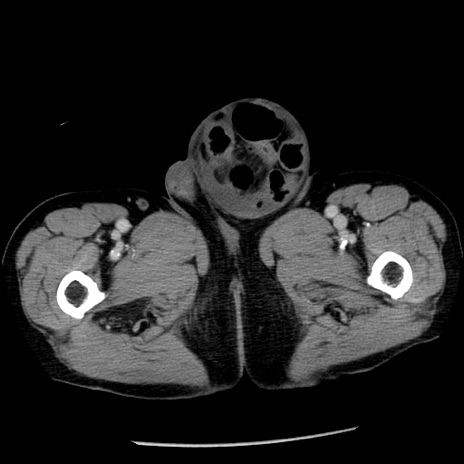

症例26(横断像)

【症例】80歳代男性

【主訴】嘔吐

【現病歴】昨晩2回嘔吐あり、今朝になっても嘔吐あり。来院。

【既往歴】胃潰瘍

【身体所見】意識清明、BT 37.6℃、BP 166/95mmHg、HR 100bpm、SpO2 97%、腹部:平坦・軟、腸蠕動音聴取良好、圧痛なし。

【データ】WBC 21900、CRP 1.46